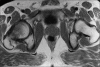

Figure 3

Coronal STIR images shows marrow edema as uniform hyperintensity signal involving head and neck of left femur and extending till the intertrochanteric region. No evidence of avascular necrosis of left femoral head